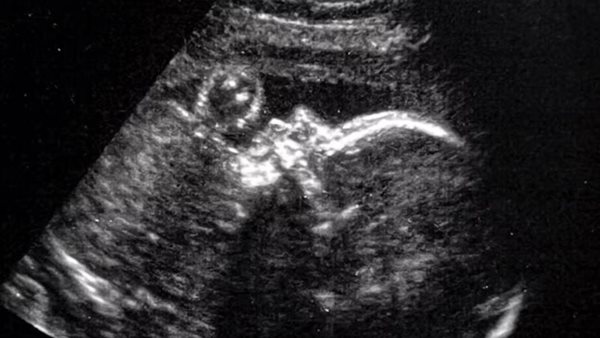

الفريق الطبي مكوّن من عشرة أفراد في مستشفى بوسطن للأطفال ومستشفى ماساتشوستس العام بأمريكا، والإجراء الدقيق تضمن قطع رحم الأم وجمجمة الجنين، ثم إجراء العملية على الدماغ النامي، من خلال استخدام الموجات فوق الصوتية لتحديد الشريان وتوجيه الجراحة.

حدد الأطباء التشوه في الأم باستخدام الرنين المغناطيسي، وحددوا الجيوب الأنفية شديدة الاتساع، والوريد المنحني في الدماغ الذي يستنزف الشريان، وهو ما أكد للجراحين أن هناك فرصة بنسبة 99٪ لحدوث التشوه.

وقام الأطباء بعد ذلك بفتح الجزء السفلي من بطن المرأة لكشف الرحم، ومن خلال الموجات فوق الصوتية لتحديد المكان الصحيح، قاموا بتقطيع جدار الرحم.

وشرع الجراحون بعد ذلك في فتح دماغ الجنين الذي لم يولد بعد، وإجراء عملية جراحية لزرع قطعة من الدهون بالقرب من الشريان والتي من شأنها تقييد تدفق الدم.